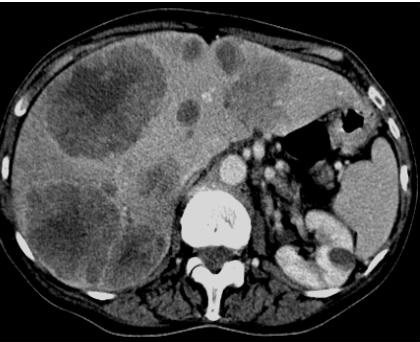

Image TDM des

metastase hepatiques : Sur la TDM a sans

preparation , aspect lesionaire souvent isodense . Les

metastase colorectale souvent hypovasculaire : lesions est

hypodenses au temps portale. Les metastases du rein souvent

hypervasculaire : lesion est hyperdense au temps arteriel

Metastase hypovasculaire du

cancer colique : Aspect lesionaire des metastase est

hypodensse au temps portal |

Metastase hypervasculaire

d'un cancer du rein : Aspect lesionaire hyperdense au temps arteriel

|